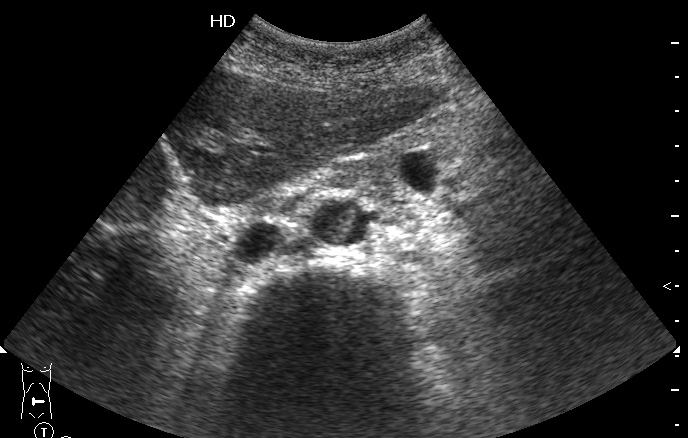

Пожилая женщина, поступила в БСМП с резкими болями в ногах. Пульс на бедренных артериях отсутствует.

Поперечный скан аорты